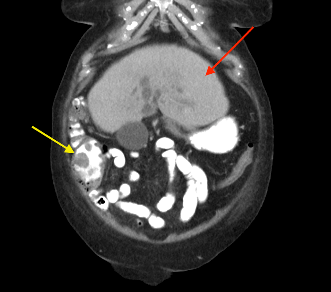

Patient had a complicated in-hospital stay which was further complicated by septic shock secondary to hospital acquired pneumonia and pericardial effusion. A repeat ultrasound liver three weeks later demonstrated a decrease in the size of the liver lesions, suggested that they favour abscess rather than metastasis. Repeat CT abdomen again confirmed the findings and also noted lobulated mucosal thickening at ileocaecal junction, suggestive of colonic neoplasm. Caecal mass was also identified in the initial CT retrospectively, which was missed initially. Colonoscopy confirmed a non-obstructing, non-circumferential mass in the caecum. Histology showed adenocarcinoma. Her liver abscess completely resolved with long course intravenous antibiotics. CT staging did not show any evidence of distant metastasis (See figure 2). An elective uncomplicated laparoscopic right hemicolectomy was performed, and she was subsequently discharged home well day six post op. Histology returned to show pT2N0M0 adenocarcinoma.

Figure 2: (a, b) Red arrow - Interval CT 2 months later illustrated significant reduction in liver mass in keeping with resolving abscesses. (b, c) Yellow arrow - Large polypoid lesion within the caecum at the ileocaecal region in keeping with carcinoma